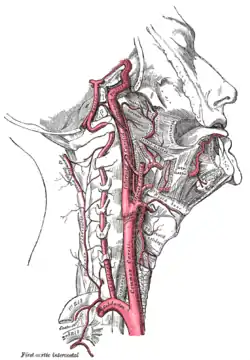

Superficial dissection of the right side of the neck, showing the carotid and subclavian arteries. | |